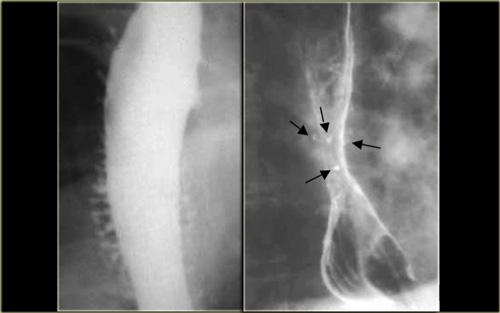

TRÁI: CT cho thấy thực quản giãn (mũi tên) dẫn đến chỉ định chụp thực quản. PHẢI: Chụp thực quản cho thấy hẹp (mũi tên) tại mức khe hoành.

Bên trái là một bệnh nhân khác bị achalasia.

TRÁI: Thực quản giãn (mũi tên) được chiếu phía sau nhĩ phải. GIỮA và PHẢI: Hẹp thuôn nhẵn ngay trên cơ hoành (mũi tên).

Trong quá trình soi huỳnh quang, quan sát thấy một số nhu động với hình ảnh hẹp thuôn nhẵn điển hình ngay trên cơ hoành (mũi tên).